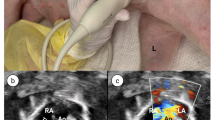

Delgado-Montero, A. et al. Blood stasis imaging predicts cerebral microembolism during acute myocardial infarction. J. Am. Soc. Echocardiogr. 33, 389–398 (2020).